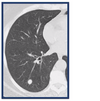

35

# Princípios básicos de tumores ósseos - De acordo com a imagens e as características listadas abaixo, classifique de acordo com Enneking: - Tumor maligno - Baixo grau - Sem metástase

- Baixo grau → **I** - Extracompartimental (extensão para partes moles visto na radiografia) → **B** - Classificação de Enneking → **I B**

36

# Princípios básicos de tumores ósseos - De acordo com a imagens e as características listadas abaixo, classifique de acordo com Enneking: - Tumor maligno - Osteossarcoma clássico de alto grau na biópsia - Sem metástase

- Alto grau → **II** - Extracompartimental (extensão para partes moles visto na radiografia) → **B** - Classificação de Enneking → **II B**